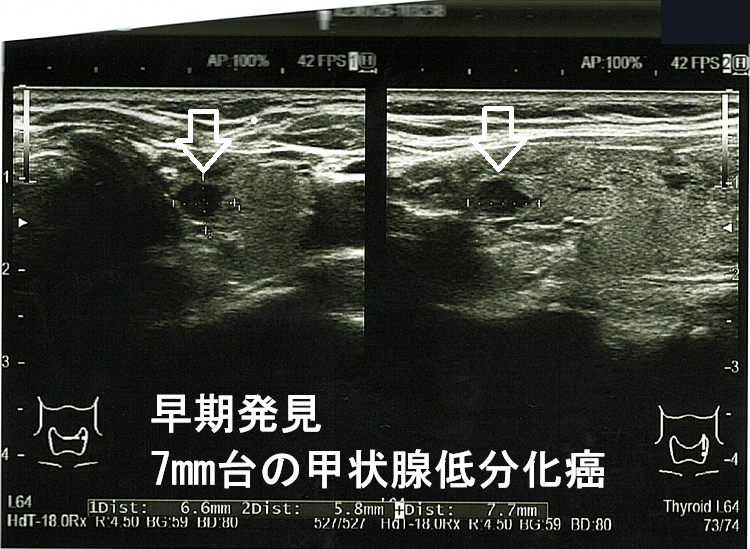

下の写真は、前項の33歳男性以外で甲状腺癌の早期発見により命が助かった事例です。

甲状腺低分化がんは、甲状腺未分化癌ほど進行が早くなく、その10年生存率は、

- stage I,II の場合、甲状腺分化癌(乳頭癌・濾胞癌) 92%、甲状腺低分化癌 81%

- stage III,IV の場合、甲状腺分化癌(乳頭癌・濾胞癌) 69%、甲状腺低分化癌 48%

(図説臨床〔癌〕シリーズ, no 11頭頸部癌 pp. 114~122, カルビュー社 (東京), 1987.)

で早期に見つけて治療するに越したことはありません。